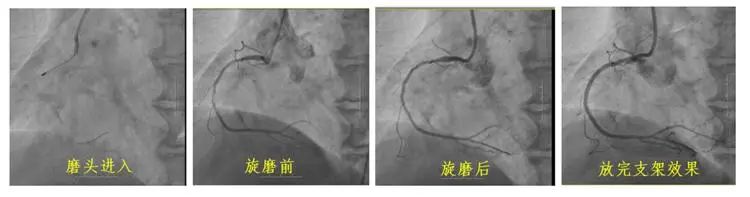

冠狀動(dòng)脈鈣化因其致密堅(jiān)硬的病變特征,長(zhǎng)期制約著心血管介入治療效果。長(zhǎng)春國(guó)文醫(yī)院心血管內(nèi)科團(tuán)隊(duì)引入冠狀動(dòng)脈旋磨技術(shù),在血管內(nèi)超聲(IVUS)實(shí)時(shí)導(dǎo)航下,以每分鐘15萬(wàn)轉(zhuǎn)旋磨技術(shù)精準(zhǔn)粉碎鈣化斑塊,成功為一名右冠狀動(dòng)脈100%閉塞的73歲患者實(shí)現(xiàn)血管再通。該技術(shù)的成熟應(yīng)用,標(biāo)志著醫(yī)院在旋磨技術(shù)處理復(fù)雜鈣化病變的臨床可靠性,為更多心血管疾病患者帶來康復(fù)希望。

冠狀動(dòng)脈旋磨術(shù)作為一項(xiàng)先進(jìn)且高難度的冠脈介入治療技術(shù),在處理冠狀動(dòng)脈嚴(yán)重鈣化病變方面具有獨(dú)特優(yōu)勢(shì)。其基于精確的“差異切割”原理,通過高速旋轉(zhuǎn)的旋磨頭,精準(zhǔn)地對(duì)鈣化或纖維化的動(dòng)脈硬化斑塊進(jìn)行祛除,同時(shí)巧妙避開有彈性的血管組織及正常冠狀動(dòng)脈,從而極大地降低對(duì)血管中膜的損傷風(fēng)險(xiǎn)。該技術(shù)具有精確性高、安全性強(qiáng)、效果持久以及適用范圍廣等顯著特點(diǎn),能夠有效減輕冠脈狹窄程度,顯著改善心肌供血狀況,為冠心病等心血管疾病的治療開辟新路徑。